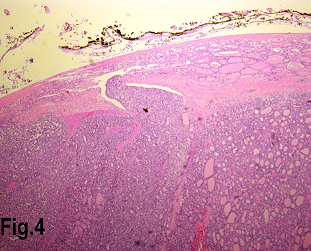

Figure 4.Low power view showing a follicular carcinoma with capsular invasion. (Hematoxylin & eosin, original magnification ×200).

Solitary benign adenomas were found in 23 cases, the peak frequency was fourth and fifth decade. Female accounted for 12 cases (70.5%) for follicular adenoma (Figure 2) and 3 cases (50%) for Hurthle cell adenoma. Thyroid malignancy and it was reported in 62 cases. Papillary carcinoma (Figure 3) was the most common type of thyroid malignancy found in 44 cases (71%) followed by follicular carcinoma (9.6%) (Figure 4), medullary carcinoma (1.6) and poorly differentiated carcinoma (1.6%) (Table 3). The peak incidence for patients with thyroid malignancy in this series was third decade and male to female ratio was 3.7:1.